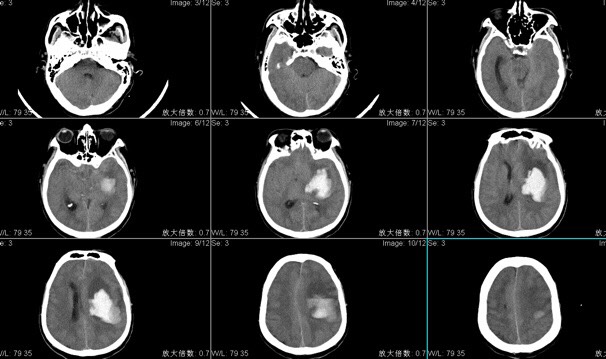

患者陈XX,男性,59岁,主因“突发右侧肢体无力伴言语含糊1小时余”入院;头CT检查显示左侧基底节区脑出血多田公式计算出血量约80ml;手术入路:神经内镜辅助经左额脑出血清除术。

术后复查头CT显示血肿清除良好,神经内镜辅助脑出血手术时间短,损伤性小恢复快